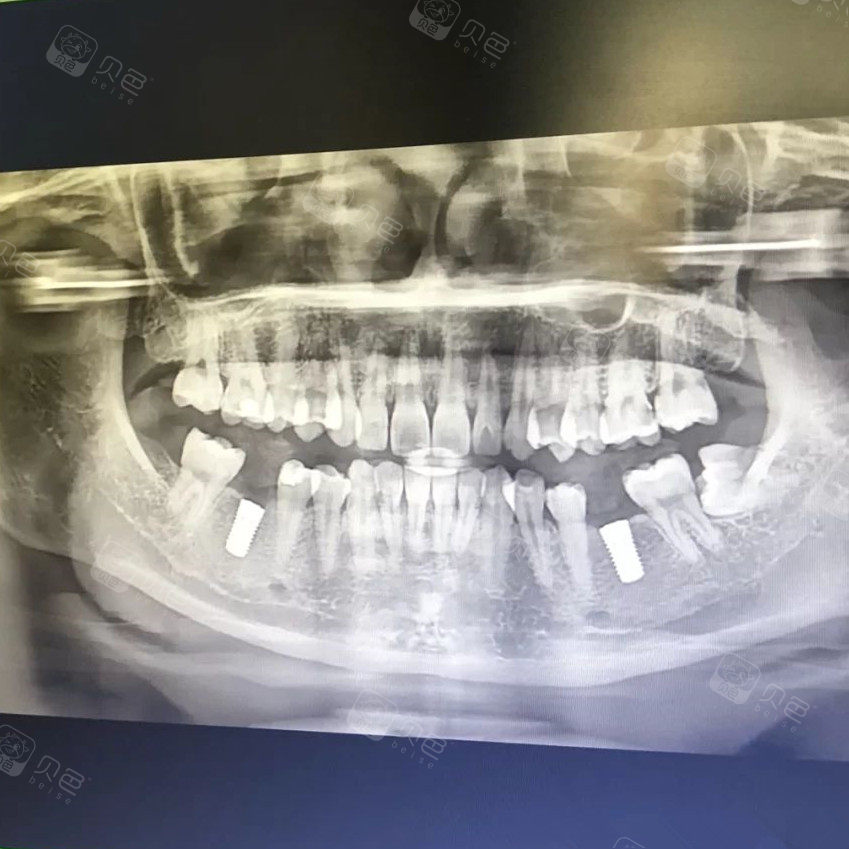

种植牙后牙片

吴女士种植带冠后的牙片显示,种植体就位准确,受力均衡据了解,如吴

第四步,去拍牙片,种植人工牙根后的片子(如下图3),拍完牙片后嘱咐:2周